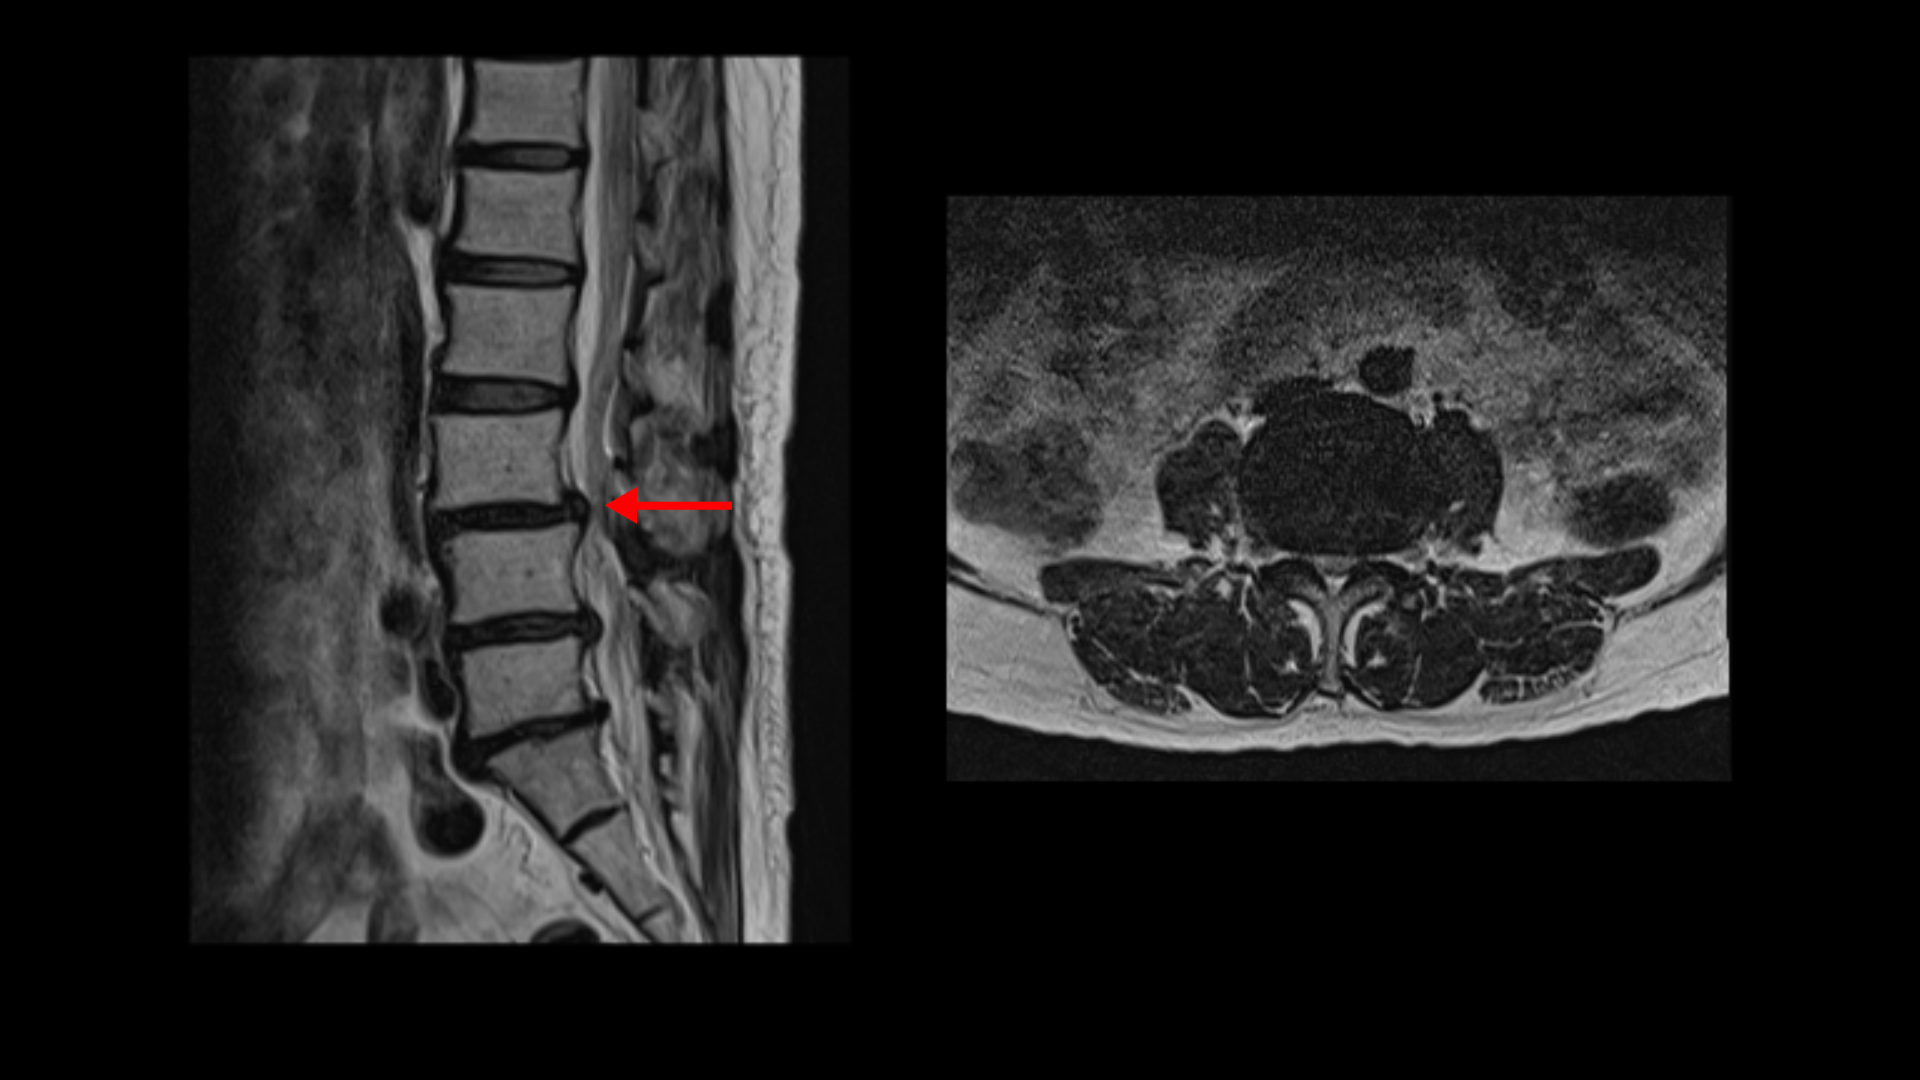

이분 MRI를 보면 3마디에 퇴행성디스크가 밀려 나와 있습니다.

또 3번 4번에는 척추전방전위증이 있습니다.

이 전방전위증 때문에 척추관에 중심성 협착도 있습니다.

4번 5번 디스크가 중앙에서 우측으로 약간 밀려 나와있고

>또 5번 1번에서는 신경이 빠져나가는 오른쪽 추간공이 약간 좁아져 있습니다.

이런 문제들 때문에 오른쪽 엉치부터 발가락까지 방사통이 있을 가능성이 있습니다. 하지만 어떤 마디가 정확한 통증의 원인인지 알기 어렵고 여러 마디가 안 좋기 때문에 이 환자분의 말씀을 들어봐도 전체적으로 여러마디 다 나사를 박자는 얘기를 들은 걸로 보입니다. 이렇게 여러 마디에 나사를 박는 유합술을 해놓으면 시간이 흘러 위나 아래에 문제가 생길 가능성도 커지고 환자분도 50대 초반의 젊은 나이라 대학병원의 교수님도 수술하기엔 너무 젊은 데라고 여러 번 말씀하셨다고 합니다. 그런데 신경 주사를 그토록 여러 번 오랜 시간 맞았는데도 환자가 심하게 아프면 수술 외에는 뾰족한 다른 방법이 없는 것이죠.

그런데 이분 허리 MRI를 자세히 보면 딱히 신경이 아주 극심하게 눌린 곳도 없습니다.

신경이 조금 눌릴 수는 있어도 심각해 보이지는 않습니다.

신경구멍이 지나가는 길이 여러 가지 퇴행성 변화로 조금씩은 좁아져 있지만 굳이 수술로 특히 여러 마디의 나사를 박는 수술까지 해가며 신경압박을 해소해야 할 정도의 심한 신경눌림은 보이지 않는 겁니다.